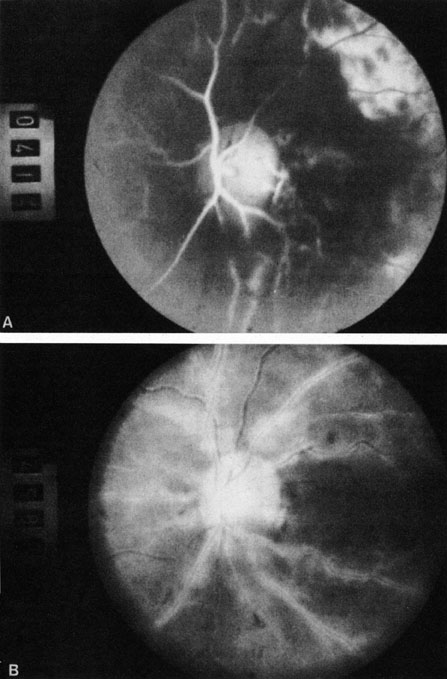

OPHTHALMIC ARTERY OBSTRUCTION

Ophthalmic artery obstruction is characterized by an initial opacification of the entire retina in a manner similar to that of central retinal artery obstruction (Fig. 4A). The cherry-red spot may or may not be present, however.119 The difference between an ophthalmic artery obstruction and central retinal artery obstruction is that in an ophthalmic artery obstruction, with time, optic atrophy develops, as does varying amounts of pigmentation due to the lack of perfusion of the retinal pigment epithelium (see Fig. 4D). This pigment is generally diffusely scattered throughout the posterior pole but it may also be seen in greater amounts in the periphery.

Fig. 4. A: Ophthalmic artery obstruction showing a cherry-red spot: the visual acuity was no light perception. B: At 26.2 seconds, the retinal vessels are filled, but no dye is seen in the choroidal circulation. C: By 37.7 seconds, the choroidal circulation is more visible, and a doughnut-shaped area of hypofluorescence is noted. D: Six months after the initial photographs, optic atrophy is present, as is atrophy of the retinal vessels. Diffuse pigment disturbance is evident.

Intravenous fluorescein angiography generally shows moderate to marked abnormalities in the filling of the choroid, in addition to a delay in filling or even nonfilling of retinal vessels (see Fig. 4B and 4C). Staining of the retinal pigment epithelium can also be seen; this staining either can occur locally in the macular area or it can be diffuse.119 The electroretinogram shows abnormalities of both a- and b-waves, reflecting ischemia to both the inner and outer retina. Almost all reported patients have had an initial visual acuity of no light perception; virtually no patients can be expected to have a final visual acuity better than that.119 An acuity of no light perception is a clue to the presence of an ophthalmic artery obstruction. Because relatively few patients with central retinal artery obstruction have an initial visual acuity of no light perception, no light perception usually suggests the likelihood of some obstruction of the choroidal circulation.14